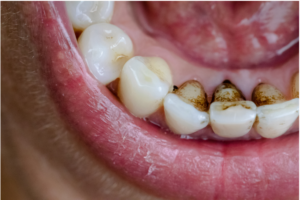

初期虫歯

初期虫歯は、虫歯菌が作る酸によって歯の表面のカルシウムやリンが少しずつ溶け出すことで始まります。

この段階では、歯の表面に白い斑点(ホワイトスポット)が現れ、ザラつきを感じることもあります。

見た目や感覚の変化は小さいため気づきにくいですが、早めにケアを行えば進行を防げます。